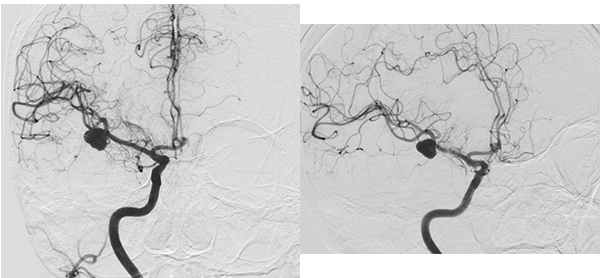

El laboratorio se encontraba dentro de parámetros normales, se realizó resonancia magnética (RM) de cerebro sin contraste, la cual mostró una imagen hipointensa en secuencia GRE a nivel del surco silviano derecho y adyacente a la misma se observa edema perilesional que se extiende al lóbulo temporal (Figura 1). Se realizó angiotomografìa para descartar una malformación vascular subyacente, en la cual se advirtió una dilatación aneurismática polilobulada de 20 x 6 x 9 milímetros (Figura 2).

Figura 2: Se observa en Angiotomografía de vasos intracraneanos en sus tres cortes anatómicos a nivel de la bifurcación de la arteria cerebral media derecha una dilatación aneurismática sacular, irregular y polilobulada sin evidencia de signos de trombosis o aterosclerosis.

Paciente femenina de 72 años de edad con antecedentes de hipertensión arterial, dislipidemia, sobrepeso y extabaquista, a quien en contexto de estudio por hipoacusia neurosensorial se le realizó RM de cerebro y conductos auditivos internos con contraste endovenoso, en la cual se observó como hallazgo incidental lesión expansiva marcadamente hipointensa en T2 localizada a nivel temporal anterior derecho de aproximadamente 23 x 14 mm de diámetro en relación con el sector distal de la arteria cerebral media homóloga. Tras la inyección de contraste presentó refuerzo heterogéneo, con un componente de aspecto trombosado en el sector basal de la misma, asociado a extenso edema periférico (Figura 3). Se decidió realizar consulta con especialidad de neurocirugía quien sugirió completar la aproximación diagnóstica con AD de vasos intracraneanos en la cual se observó a nivel silviano derecho dilatación aneurismática de contornos lobulados con diámetros de 10.7 x 9.7mm, no presentando un cuello favorable para el acceso endovascular (Figura 4 y 5). En dicho estudio se menciona además pequeño aneurisma de 2mm en arteria comunicante anterior y otro silviano izquierdo de 4mm.

Figura 4: Estudio por AD. Tanto en la imagen de la izquierda (vista anterior) y derecha (vista lateral) se observa a nivel silviano derecho dilatación aneurismática de contornos lobulados con diámetros aproximados de 10.7 x 9.7 mm.